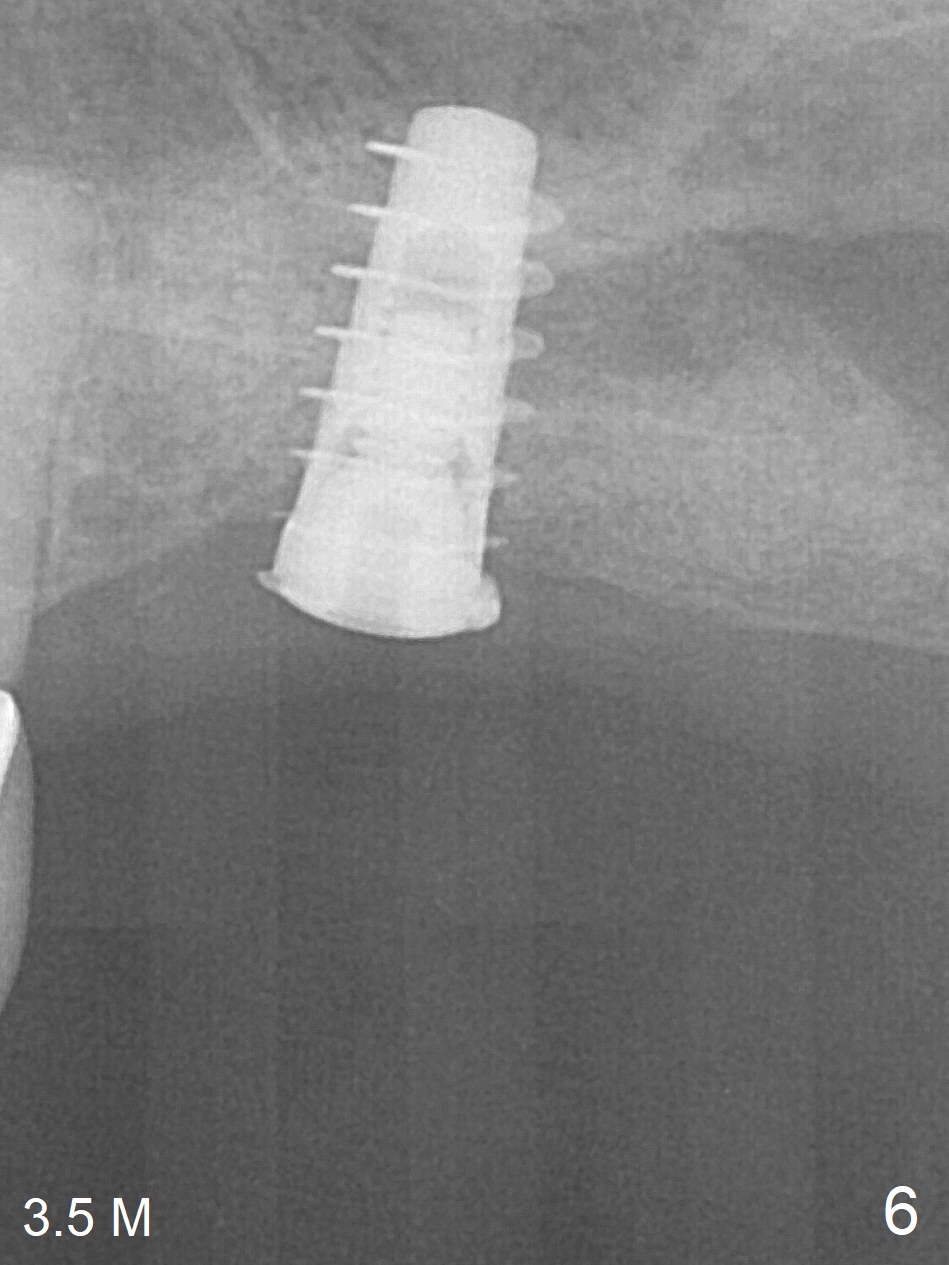

The bone graft appears to move distal 1 month 20 days postop (Fig.5 arrow), while the implant seems to be extruded with implant exposure. The patient feels pain when the healing screw is being removed or tightened. The distal migration of the bone graft may lay foundation for future implant placement at #15. Bone density around the implant remains the same (Fig.6), while the wound reduces nearly 3.5 months postop (Fig.7). The healing screw cannot be turned without causing pain. Can the implant at #14 be retorqued to be seated deeper 3-4 months later?